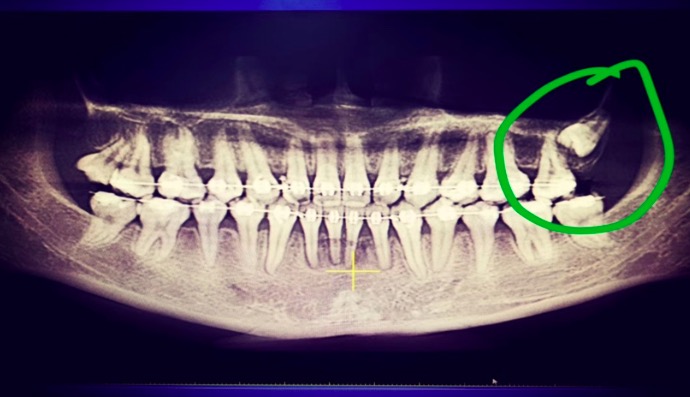

下图为来我院拔除的常见阻生智齿

病人为22岁的女性,现处于正畸治疗阶段。在感觉到左上牙咀嚼无力就及时来我院就诊。刘建华医生在x光片检查后发现,左上第三磨牙为低位阻生,压迫第二磨牙牙根,导致第二磨牙咀嚼无力,偶有酸软感。当时决定拔出。这位患者对拔牙有恐惧,拔牙前十分害怕,但是过程无痛,拔牙后表示非常轻松。